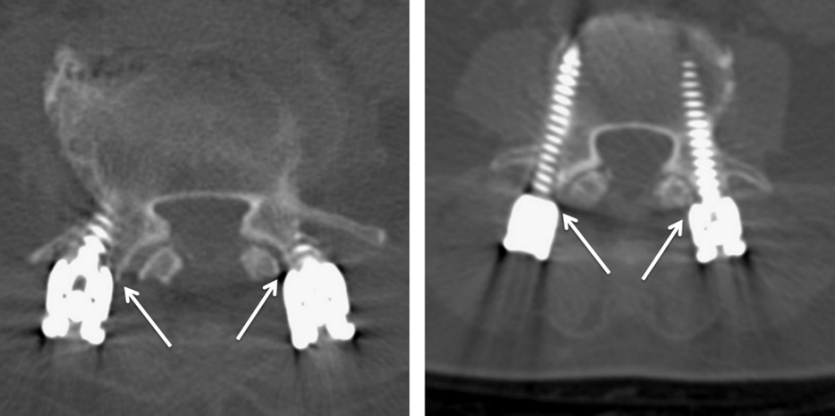

对于椎弓根螺钉损伤关节突关节的影像学评估,目前已有的临床研究主要依据内固定术后CT扫描观察螺丝、螺帽或连接杆对关节突关节的损伤程度。本期我们将已有的分级系统进行汇总,为大家术后评估和进一步研究提供参考。

2.Badu分级

0级:螺钉没有触及关节

1级:螺钉触及关节侧缘,但未进入关节腔内

2级:螺钉进入关节腔内,但进入距离<1 mm(右)

3级:螺钉进入关节腔内,进入距离≥1 mm